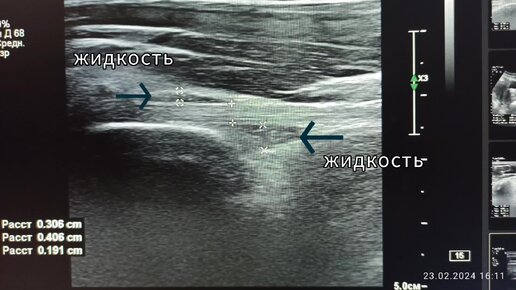

Начинающим врачам УЗИ: сухожилие и жидкость над и под ним